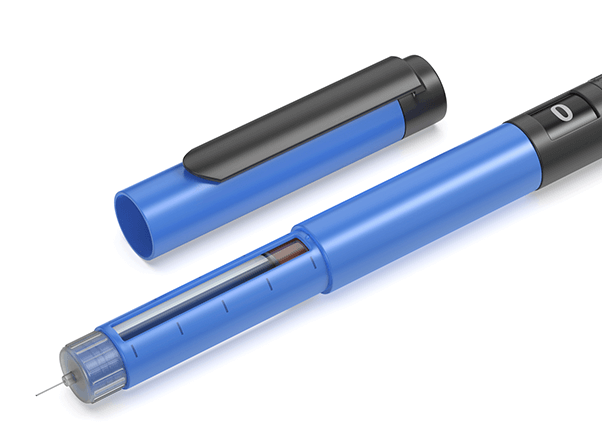

成長ホルモン注射

成長ホルモン療法は、通常、毎日または週1回の自己注射によって行います。

使用する注射器はペン型が主流で、針は非常に細く、皮下に浅く注射するため痛みは最小限です。多くの方が数回で慣れ、日常生活に大きな負担なく継続できます。

当院では、初回時に専門スタッフが実演を交えた丁寧な指導を行い、患者さまやご家族が安心して自宅で行えるようサポートします。また、注射のタイミングや部位のローテーション、保管方法なども分かりやすくご案内し、必要に応じてフォローアップも実施しています。

治療を長期的に安全かつ効果的に続けるため、「痛みの少なさ」「操作の簡便さ」「継続しやすい環境」を重視しています。 -

注入デバイス代

(初回のみ)3,000円(税込)